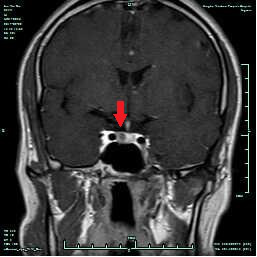

CASE3 病人***男性,30岁,因“性功能下降、不育5年”入院,入院诊断垂体泌乳素微腺瘤。

在全麻下行经鼻蝶内镜下垂体微腺瘤切除术,术后病人泌乳素指标恢复正常,性功能有一定改善。(红色箭头示黑色圆点为垂体微腺瘤;蓝色箭头示术后3个月复查未见肿瘤显示)